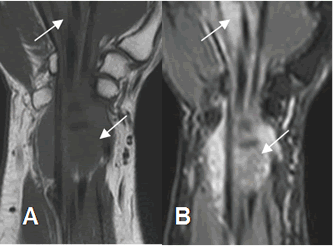

Fig 95 B. Fibromatosis.

A: RM coronal en T1 y B: RM coronal en STIR. Tejido inflamatorio agudo hipointenso en T1 e hiperintenso en STIR, rodeando los tendones flexores, a nivel de la muñeca y la palma de la mano.